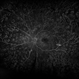

- Diabetic Retinopathy

- laser scarring

- Jason S. Calhoun, Department of Ophthalmology, Mayo Clinic Jacksonville, Florida

Fundus camera

TOPCON TRC 50-EX - Description

- Fundus montage shows retinal hemorrhage with laser scars due to diabetic retinopathy in the right eye.